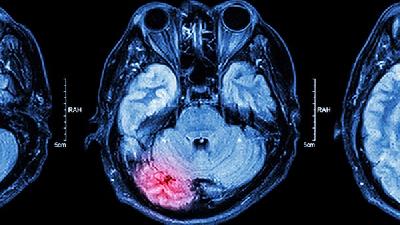

小儿脑瘫也就是小儿患有了脑性瘫痪,主要指的就是小儿在出生前或者是出生之后就患有的脑损伤疾病,此种疾病的主要症状就表现为中枢性运动障碍以及姿势异常等,小儿一旦患有了这种疾病,就会导致很多的家庭都陷入黑暗的深渊,所以一定要及时的预防此病的发生,那么如何预防新生儿脑瘫呢?

脑瘫可能由产前缺氧、早产低体重、新生儿黄疸、遗传代谢异常等原因引起,症状表现为运动障碍、肌张力异常等,需通过康复...

脑瘫的临床表现主要有运动发育迟缓、肌张力异常、姿势异常、伴随症状等,需根据具体类型综合评估。 1. 运动发育迟缓...

小儿脑瘫的症状表现主要包括运动发育迟缓、肌张力异常、姿势反射异常、语言障碍等,严重者可伴随智力障碍或癫痫发作。 ...